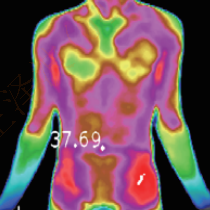

Diagnosis of swelling, heat pain and general pain

When muscles are injured or inflamed, neuropathy and other symptoms cause locally poor blood flow and nerve conduction, all of which will cause abnormal expression of body metabolism. Medical thermographic cameras can accurately detect pain spots and inflammation areas, as a grading diagnosis of pain, accordingly, they can give a targeted treatment plan.